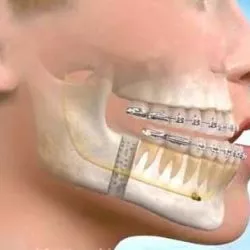

בטיפול המשלב בין יישור שיניים לניתוח בלסתות, יתכננו המומחה לכירורגית הפה והלסתות והאורתודונט את המיקום החדש של הלסתות הן מבחינה אסתטית והן מבחינה תפקודית, דבר שיאפשר מיקום נכון של השיניים במנשך תקין.

תזוזת השיניים תתבצע לעיתים לפני התהליך הניתוחי, לעיתים אחריו ולעיתים גם לפני וגם אחרי.